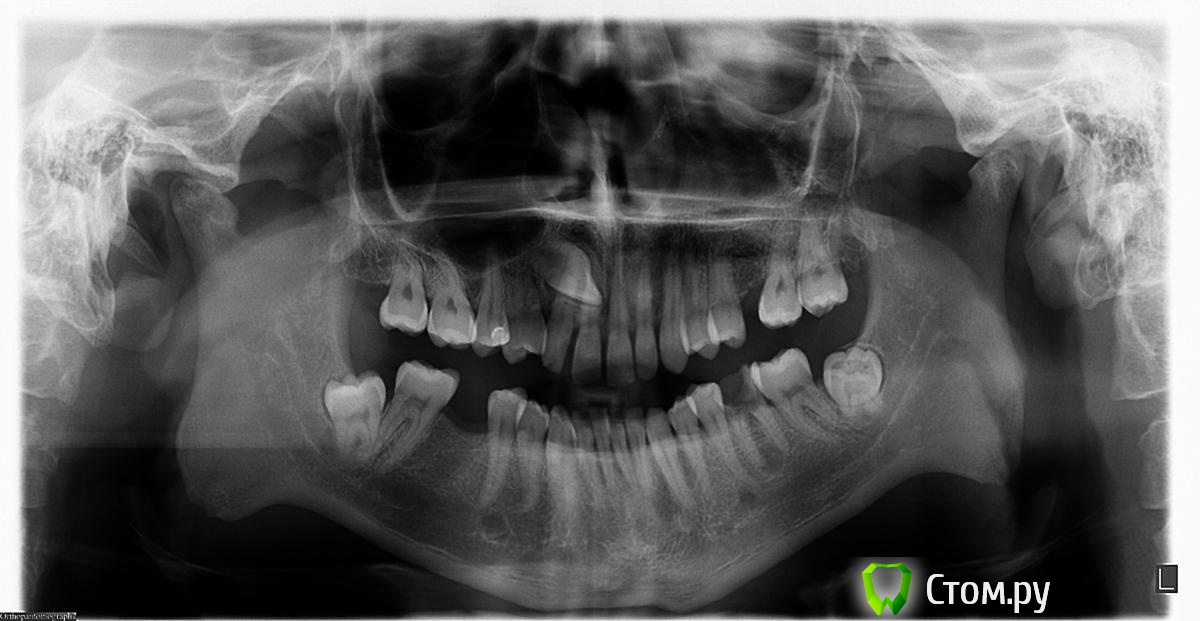

mikl Опубликовано 21 мая, 2014 Автор Поделиться Опубликовано 21 мая, 2014 Снимок Ссылка на комментарий

mikl Опубликовано 22 мая, 2014 Автор Поделиться Опубликовано 22 мая, 2014 (изменено) Разумеется и это практически классическая симптоматика TMD.А можно это как-то подтвердить или дополнительное исследование какое-нибудь? Например, у меня с носом тоже беда, он не дышит уже практически и запахов почти не чувствую уже давно. И с шеей тоже проблемы 3 протрузии небольшие. Но, ЛОРы говорят, что по их части ничего страшного, и неврологи тоже как-то отмахиваются. ПТ только с распростертыми объятиями встречают. Я скажу, что изначально, когда у меня появился звон и заложенность это я точно представлял для себя так. Раньше, когда все было хорошо, если я зевал, то на пике зевания у меня начинался такой звон в голове и уши оглушало изнутри. Ну, т.е., когда я зевал у меня был звон в голове, и я в этот момент плохо слышал. Я и думал, что так у всех. Но потом поспрашивал, все на меня как на дурака смотрели, мол у них нет такого. И вот сейчас этот звон и оглушенность очень напоминают то состояние пика зевоты, как будто я зевнул и в таком пиковом состоянии со звоном и оглушенностью остался.Ну, наверное, если это только у меня при зевании так, то это трудно понять будет Ссылка на архив с МРТ. Делал У Риден Татьяны Владимировны. http://www.fayloobmennik.net/3820017 Еще что могу добавить. С левой стороны, снизу, был зуб без пломбы, один корень почти. Видно на панораме. Очень долго я с ним жил и по этому жевал валько правой стороной. После снимка мне его удалили. Кстати, потом челюсть болела, а потом через несколько дней хрустнула и перестала болеть, видимо при удалении сдвинули или еще что. Но сейчас не болит. Хрустит как прежде. И очень неприятные ощущение, если надавливать между мочкой уха и челюстью во впадинку, слева больнее. И шарик там больше по размеру. Изменено 22 мая, 2014 пользователем mikl Ссылка на комментарий